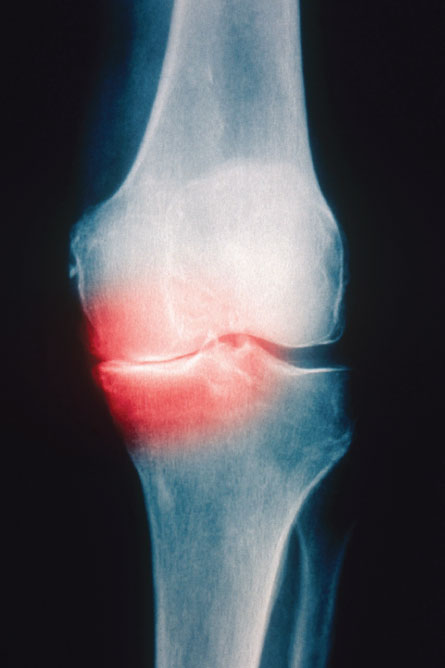

It’s not a good scenario for an aging population. As the go-between tissue in joints, cartilage can handle only so many jolts and jars before something has to give. When the daily grind wears the tissue down, or it gets damaged by more abrupt injury, the bones’ nerve cells become exposed. Movement can lead to a painful zing, the hallmark of osteoarthritis, which now affects more than 27 million people in the United States. In addition to pain, osteoarthritis shows up as stiff joints, cracking sounds, inflammation and bone spurs.

Cartilage is made to handle stress and compression, but every tissue has its limits, and knee injury increases by sixfold the likelihood that a person will develop osteoarthritis. Felson says his team has found evidence that injuries to the knee structures “probably account for a great majority of osteoarthritis.”

But early detection isn’t easy since many people ignore or underestimate their injuries. Years can pass before X-rays and other scans show two bones rubbing together, a sign of painful cartilage loss and budding osteoarthritis.